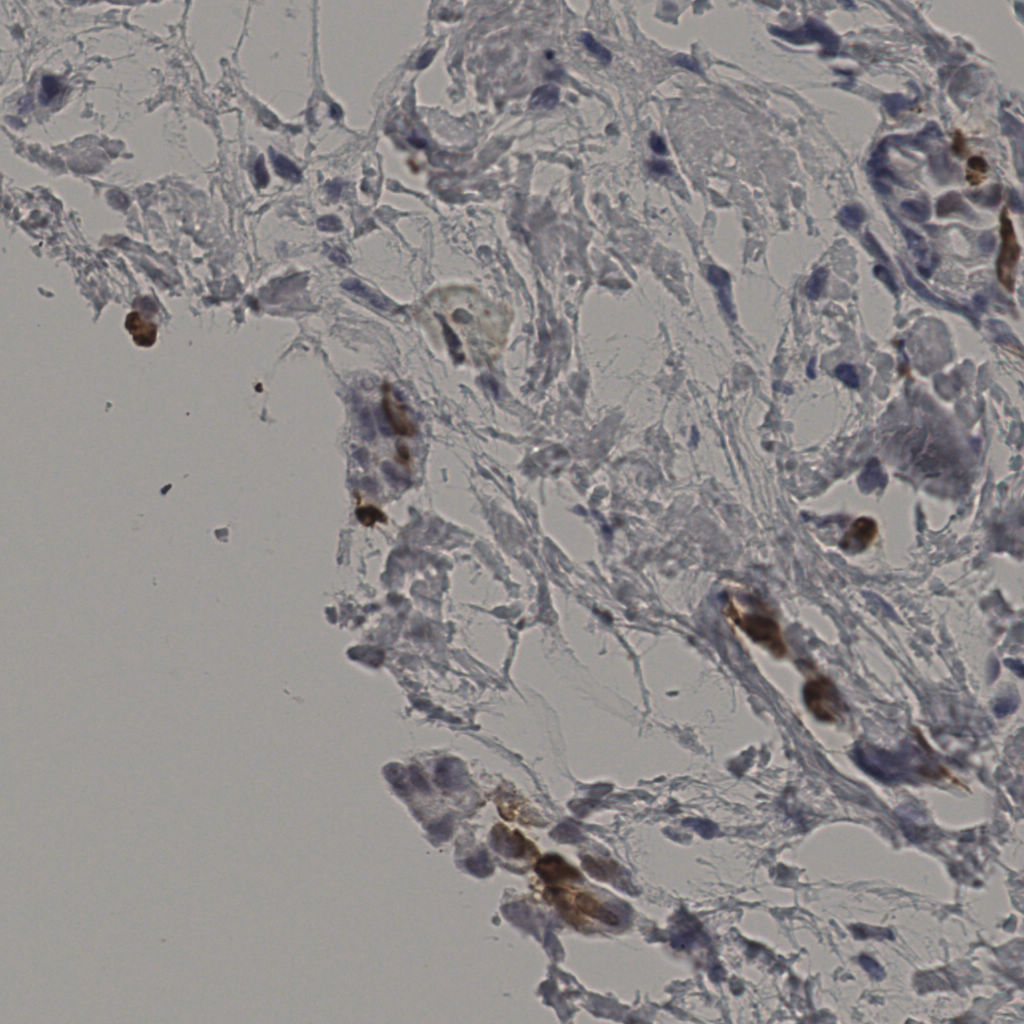

5.31%

Ki67 指数

阴 19502

阳 1093

切片统计

总切片

2970

有效

554

已标记

554

有效率

19%